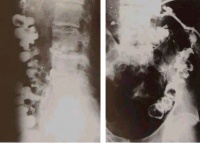

(二)骨形改变。管状长骨的破坏可表现为不同程度的膨胀变形,脊椎的椎体结核、椎体坍塌可呈楔状变形,椎体上下之间相互嵌入出现驼背或龟背畸形等。

脊柱是骨结核最常见的发病部位,尤其是在老年人群;但是在发展中国家,儿童和青少年发病的也很常见。有些病人能发现肺或泌尿系有原发结核病灶,也有些病人找不到原发灶。淋巴和血行播散的结核一般发生在胸腰段,很少播散到颈椎和骶骨。脊柱结核的活动性病变破坏特定的椎体节段:通常是相临的两个椎体和椎体之间的间盘。一些研究者推测,病变破坏的这种特点的原因是:该部位动静脉血供丰富,而结核杆菌需要高的氧分压。

约80%的病人为间盘周围病变,侵及椎体前部,最后经韧带下间隙(前纵韧带)发展到相临的椎体。少数病人病变发生在椎体中央,这种病变可类似肿瘤或者引起明显的脊柱畸形,有时很难诊断。病人可能会有髓内肉芽肿、蛛网膜炎、椎体节段性塌陷形成的前方楔形变、驼背(Pott病)等。单纯的脊柱后部结构结核很少见。有时会形成椎旁脓肿并形成皮肤窦道,侵及同一平面的腹腔脏器。椎旁脓肿最远可到达腘窝。病人会有疼痛、无力,到晚期会出现截瘫。